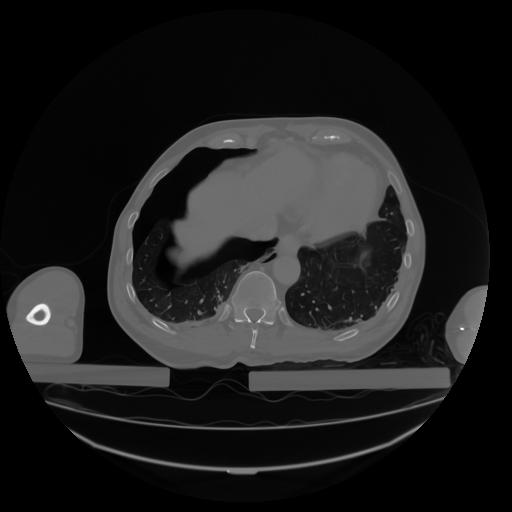

27 CUERPO,CE,Axial,3.0,CUERPO,,